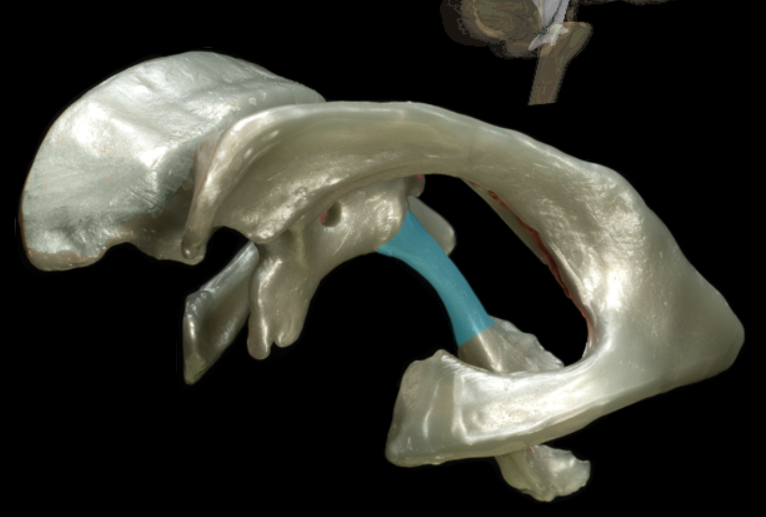

tentorium cerebelli